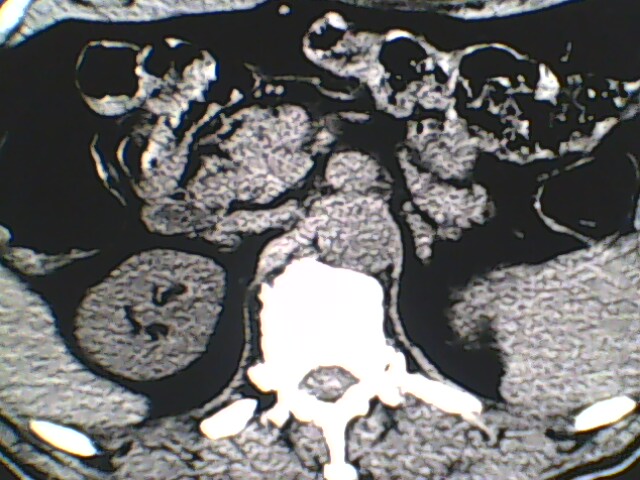

男,56岁,高血压,临床怀疑肾上腺问题,肝脏怎么那么高啊?能描述一下么?

右侧膈膨升,间位结肠,胸腰椎退行性骨关节病,右侧肾上腺可疑增生(图像颗粒太粗,窗太窄,不好看)。

支持 右侧膈膨升,间位结肠;胸腰椎退行性骨关节病;双侧肾上腺可疑增生。